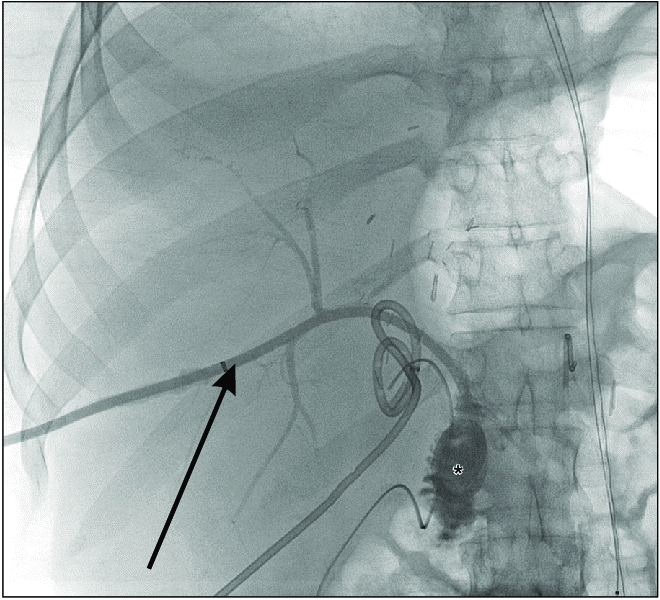

Can thiệp dẫn lưu đường mật ra da dưới hướng dẫn của điện quang

Nguồn: Percutaneous-transhepatic creation of a bilioenteric neoanastomosis in a patient with bile duct injury using cone-beam computed tomography. DOI:10.18528/ijgii180037